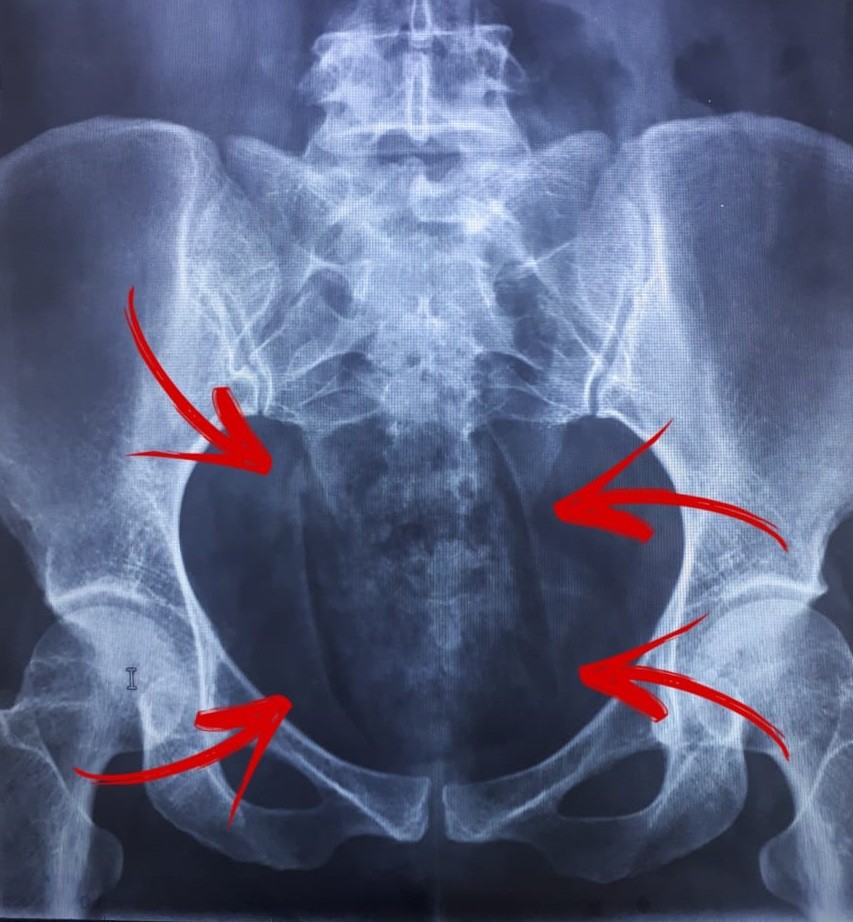

Foi nessa quinta-feira (26), em Paranavaí. De acordo com a Polícia Civil, havia uma denúncia de que duas mulheres tentariam entrar com drogas no minipresído da cidade. As duas foram submeteram a um exame de raio-x.

No exame foi constatado que havia algo na vagina das duas. Ainda segundo a PC, uma escondia 27 gramas de maconha, e outra 155 gramas. Elas foram autuadas por tráfico de drogas, conforme a polícia. A droga foi apreendida.